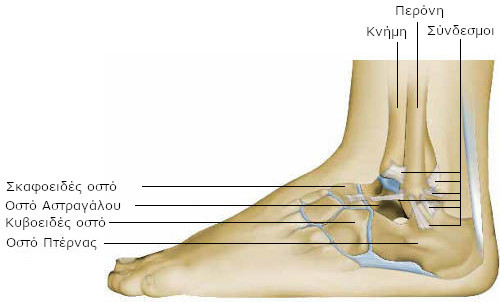

Η ποδοκνημική (άρθρωση του αστραγάλου) είναι η άρθρωση που ενώνει την κνήμη (γάμπα) με το άκρο πόδι. Επιτρέπει να σηκώνουμε και να χαμηλώνουμε το άκρο πόδι (κινήσεις κάμψης/έκτασης) και παίζει σημαντικό ρόλο στο περπάτημα.

Ακριβώς κάτω από την ποδοκνημική υπάρχει μια άλλη άρθρωση, η άρθρωση του ταρσού, η οποία επιτρέπει τις κινήσεις του ποδιού προς τα αριστερά και τα δεξιά (περιστροφικές κινήσεις).

Η ποδοκνημική άρθρωση ενώνει τα δύο οστά της γάμπας (την κνήμη και την περόνη) με ένα οστό του άκρου ποδός (τον αστράγαλο).

Η άρθρωση του ταρσού αποτελείται από διάφορες μικρότερες αρθρώσεις, που συνδέουν τα οστά του άκρου ποδός:

- υπαστραγαλική άρθρωση, ανάμεσα στον αστράγαλο και την πτέρνα,

- αστραγαλοσκαφοειδή άρθρωση, ανάμεσα στον αστράγαλο και το σκαφοειδές οστό,

- πτερνοκυβοειδή άρθρωση, ανάμεσα στην πτέρνα και το κυβοειδές οστό.

Μια σχετικά μαλακή επιφάνεια (ο χόνδρος) επιτρέπει στα οστά να γλιστρούν μεταξύ τους χωρίς τριβές.

Τα οστά συγκρατούνται μεταξύ τους με ένα είδος μαλακών και ανθεκτικών ταινιών (τους συνδέσμους) και τους μυς.